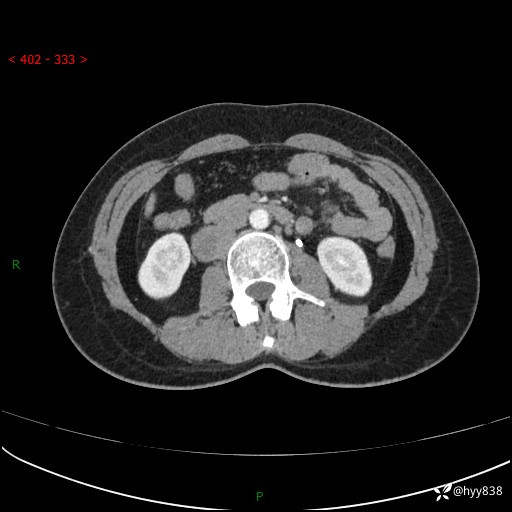

现在都流行跨界,病变也不例外,从腹膜后长到胸腔了---结果公布~

主诉:体检发现右侧腹膜后肿物1天

简要病史:患者于1天前因体检发现右旁肾占位,无肉眼血尿,无畏寒发热,无咳嗽咳痰,无腰腹部疼痛不适,无尿频尿急症状,起病来,患者未行特殊治疗,为求进一步诊治,门诊以"右侧腹膜后肿物"收治入院。 发病来患者精神、饮食、睡眠良好,小便如上,大便正常,体重无明显变化。

临床诊断:腹膜后肿物

上腹部CT增强(动脉期+实质期)(外院平扫)